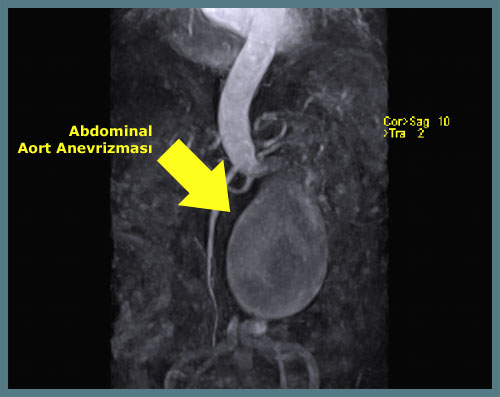

Anevrizma tanısında özellikle tedaviyi planlamak için başka yöntemlerde kullanılmaktadır. Bunlar bilgisayarlı tomografi, manyetik rezonans görüntüleme ve anjiografidir.

Bu yöntemler ile anevrizmanın ne kadar büyük olduğu (tedavi planlamasının en önemli öğesidir), nerede olduğu ve hangi organlarla ilişkide olduğu belirlenir. Anjiografi cerrahi girişimi plnalamak için genelde gerekmez, ama endovasküler anevrizma onarımı planlanırken çektirilmesi uygundur.